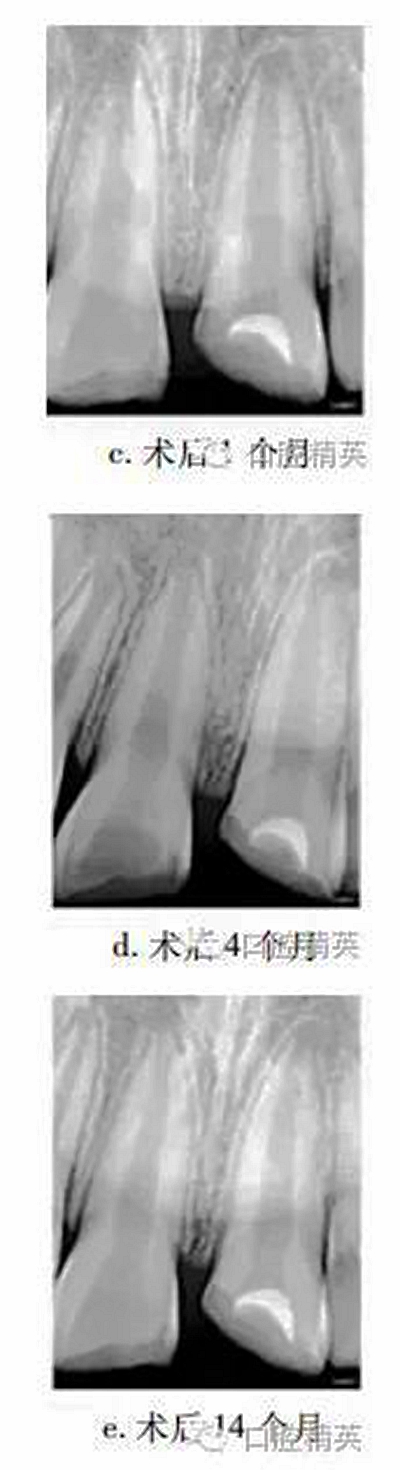

1個(gè)月后復(fù)查,21無(wú)明顯不適,上唇腫脹減輕,患牙冷熱診(-),牙髓電活力測(cè)試(-),X線片示根尖無(wú)明顯變化(圖c)。4個(gè)月后復(fù)查,患牙無(wú)明顯不適,冷熱診(±),牙髓活力測(cè)試(-),X線片示患牙根管腔略見縮窄(圖d)。14個(gè)月后復(fù)查,患牙無(wú)明顯不適,牙髓活力測(cè)試(+),但較正常對(duì)照牙低;X線片示:蓋髓劑下方可見斷斷續(xù)續(xù)的高密度影像,根管壁增厚,管腔明顯縮窄,根尖孔聚攏傾向,牙根長(zhǎng)度較初診時(shí)增加(圖e)。患牙原充填物略有缺損,稍加預(yù)備后玻璃離子暫時(shí)恢復(fù)牙冠形態(tài)。